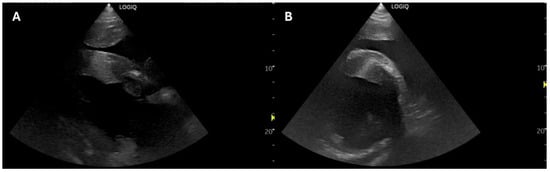

2.1. Case 1

2.2. Case 2

2.3. Case 3